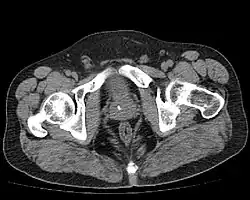

Диагноз устанавливается на основании пальцевого ректального исследования простаты, данных ультразвукового и рентгеновского исследования. При пальцевом ректальном исследовании выявляется плотный участок в ткани предстательной железы, в ряде случаев определяется крепитация. Возможно отсутствие каких-либо изменений при пальцевом исследовании простаты. Изменения, обнаруженные при исследовании предстательной железы пальцем, необходимо дифференцировать с раком и туберкулезом предстательной железы. При УЗИ простаты (трансректальном или трансабдоминальном) обнаруживаются гиперэхогенные участки в предстательной железе с формированием акустической дорожки. Размеры камней варьирует от 3 до 25 мм и более. Множественные камни наблюдаются примерно в 70 % случаев. При рентгеновском исследовании выявляют около 30 % камней предстательной железы, так как большинство камней рентгеннегативные[3]. В качестве дополнительных методов визуализации могут быть использованы КТ и МРТ таза. Наличие бессимптомных камней простаты само по себе не оказывает влияние на объём предстательной железы и уровень ПСА в сыворотке крови[7].